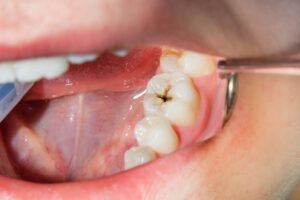

अगर आपके दांतों पर काले या भूरे रंग के धब्बे दिखें, दांत में छोटा छेद महसूस हो, ठंडी-गरम चीजों से Sensitivity हो, मीठा खाने पर चुभन हो, हल्का या तेज दर्द हो, खाना दांतों में फंस जाए, सांस से बदबू आए या दांत कमजोर होकर टूटने लगे, तो ये संकेत हैं कि आपके दांत में कीड़ा लग गया है। दांतों से जुड़ी परेशानियों में यह सबसे आम समस्या है जिससे कई लोग पीड़ित रहते हैं।

इस बारे में हमने खुल्बे डेंटल केयर एंड इम्प्लांट सेंटर की डेंटिस्ट डॉ. तेजस्वी भट्ट खुल्बे (गोल्ड मेडलिस्ट) से बात की। उन्होंने बताया कि दांत में कीड़ा लगना दरअसल बैक्टीरियल संक्रमण के कारण दांत में छेद (कैविटी) बनने की प्रक्रिया है। यह काला धब्बा छोटे से शुरू होकर दांत की नस तक पहुंच सकता है। यदि समय पर इलाज न कराया जाए तो इसके कारण तेज दर्द, संवेदनशीलता बढ़ना और दांत टूटने जैसी गंभीर समस्याएं हो सकती हैं।

कैविटी बनने के बाद कोई भी घरेलू उपाय इसे ठीक नहीं कर सकता क्योंकि यह अंदर से सड़ी हुई और संक्रमित होती है। इसे केवल डेंटिस्ट की मदद से ही सही तरीके से साफ किया जा सकता है। डॉक्टर एक खास उपकरण से दांत के सड़े हुए हिस्से और उसमें मौजूद बैक्टीरिया को पूरी तरह साफ करते हैं। इसके बाद दांत में बने छोटे छेद को कंपोज़िट मटेरियल से भर दिया जाता है, जिसे फिलिंग कहते हैं। फिलिंग करवाने से दांत मजबूत हो जाता है, कैविटी बढ़ना रुक जाता है, दर्द बंद हो जाता है और दांत फिर से सड़ने से बच जाता है।